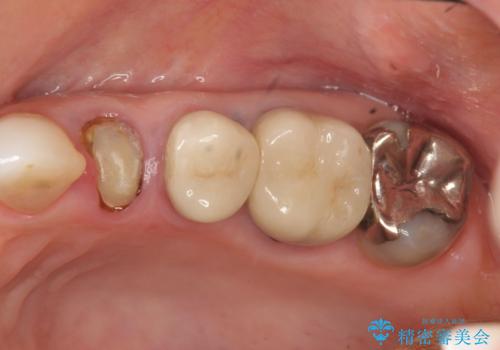

- 97.9万円(インプラント×2・アバットメント×2・仮歯×2・ジルコニアクラウン×2・骨造成)費用は治療当時の料金となります

今回はが原因で失われてしまった骨の幅を回復することで長期的な予後を見込めるインプラント治療を行うことができました。